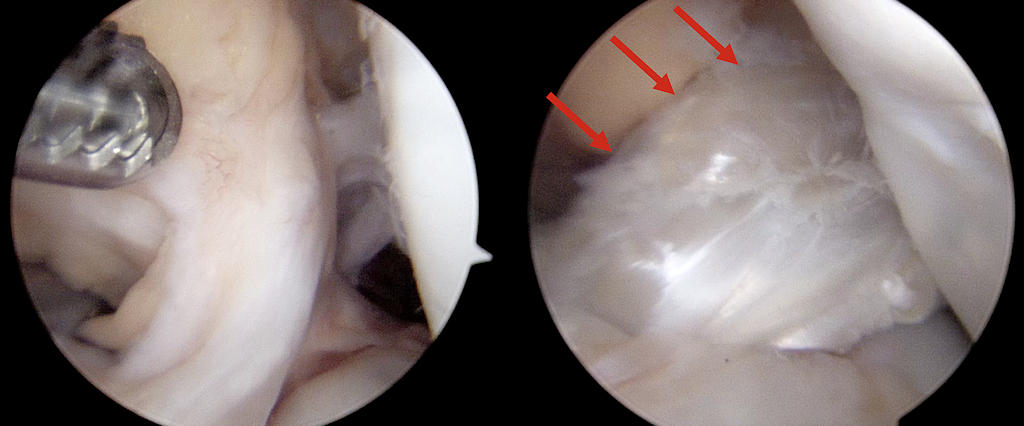

Genç yaşlarda spora katılımın artması ve giderek daha rekabetçi hale gelmesi, büyümesi tamamlanmamış çocuk ve ergenlerde ön çapraz bağ yaralamalarının görülme sıklığını artırmıştır. Çocuklarda ön çapraz bağ yaralanmaları kemik yapışma yerinden kopma kırıkları şeklinde olabileceği gibi, bağın gövdesinden olan yırtılmalar şeklinde de karşımıza çıkabilir (Resim 1). Bu yaşlarda yapılacak cerrahi işlemlerin çocuğun büyümesini olumsuz etkileyeceği endişesi ile uzun yıllar bu çocuklarda ameliyatlı tedavilerden kaçınılmış ve spor düzeyinin azaltılması ve fizik tedavi yöntemleri ile büyüme tamamlanana kadar beklenmesi benimsenmiştir. Ancak son yıllarda yapılan çalışmalarda, tekniğine uygun yapıldığında çocuklarda ve ergenlerde yapılacak ön çapraz cerrahilerinin büyüme kusuruna yol açma riskinin çok düşük olduğu saptanmıştır. Üstelik bu çocuklar tedavisiz bırakıldığında ortaya çıkacak olan menisküs ve kıkırdak hasarlarının geri dönüşü yoktur. Bu nedenlerden dolayı günümüzde çocuk ve ergenlerdeki ön çapraz bağ yaralanmalarının tedavisinde cerrahi seçenekler öne çıkmaktadır.

Erişkinlerde görülen ön çapraz bağ yaralanmalarında bağ genellikle dikilemeyecek kadar parçalanmıştır, bu nedenle diz çevresi kaslarından alınan kirişler ile yeniden bir bağ yapılır. Çocuk ve ergenlerde ise, bağın yapışma yerinden sıyrılarak ayrılması daha yüksek oranda görülür. Bu hastalar ilk 3 hafta içinde saptandığında, bağın gövdesinin bütünlüğü korunduysa, ön çapraz bağ kopmuş olduğu kemiğe dikişler ile tamir edilebilir. Buna karşın, bağın gövdesi görev yapamayacak şekilde parçalandıysa, erişkinlere benzer şekilde diz çevresi kasların kirişleri kullanılarak yeni bir bağ yapılması gerekir.